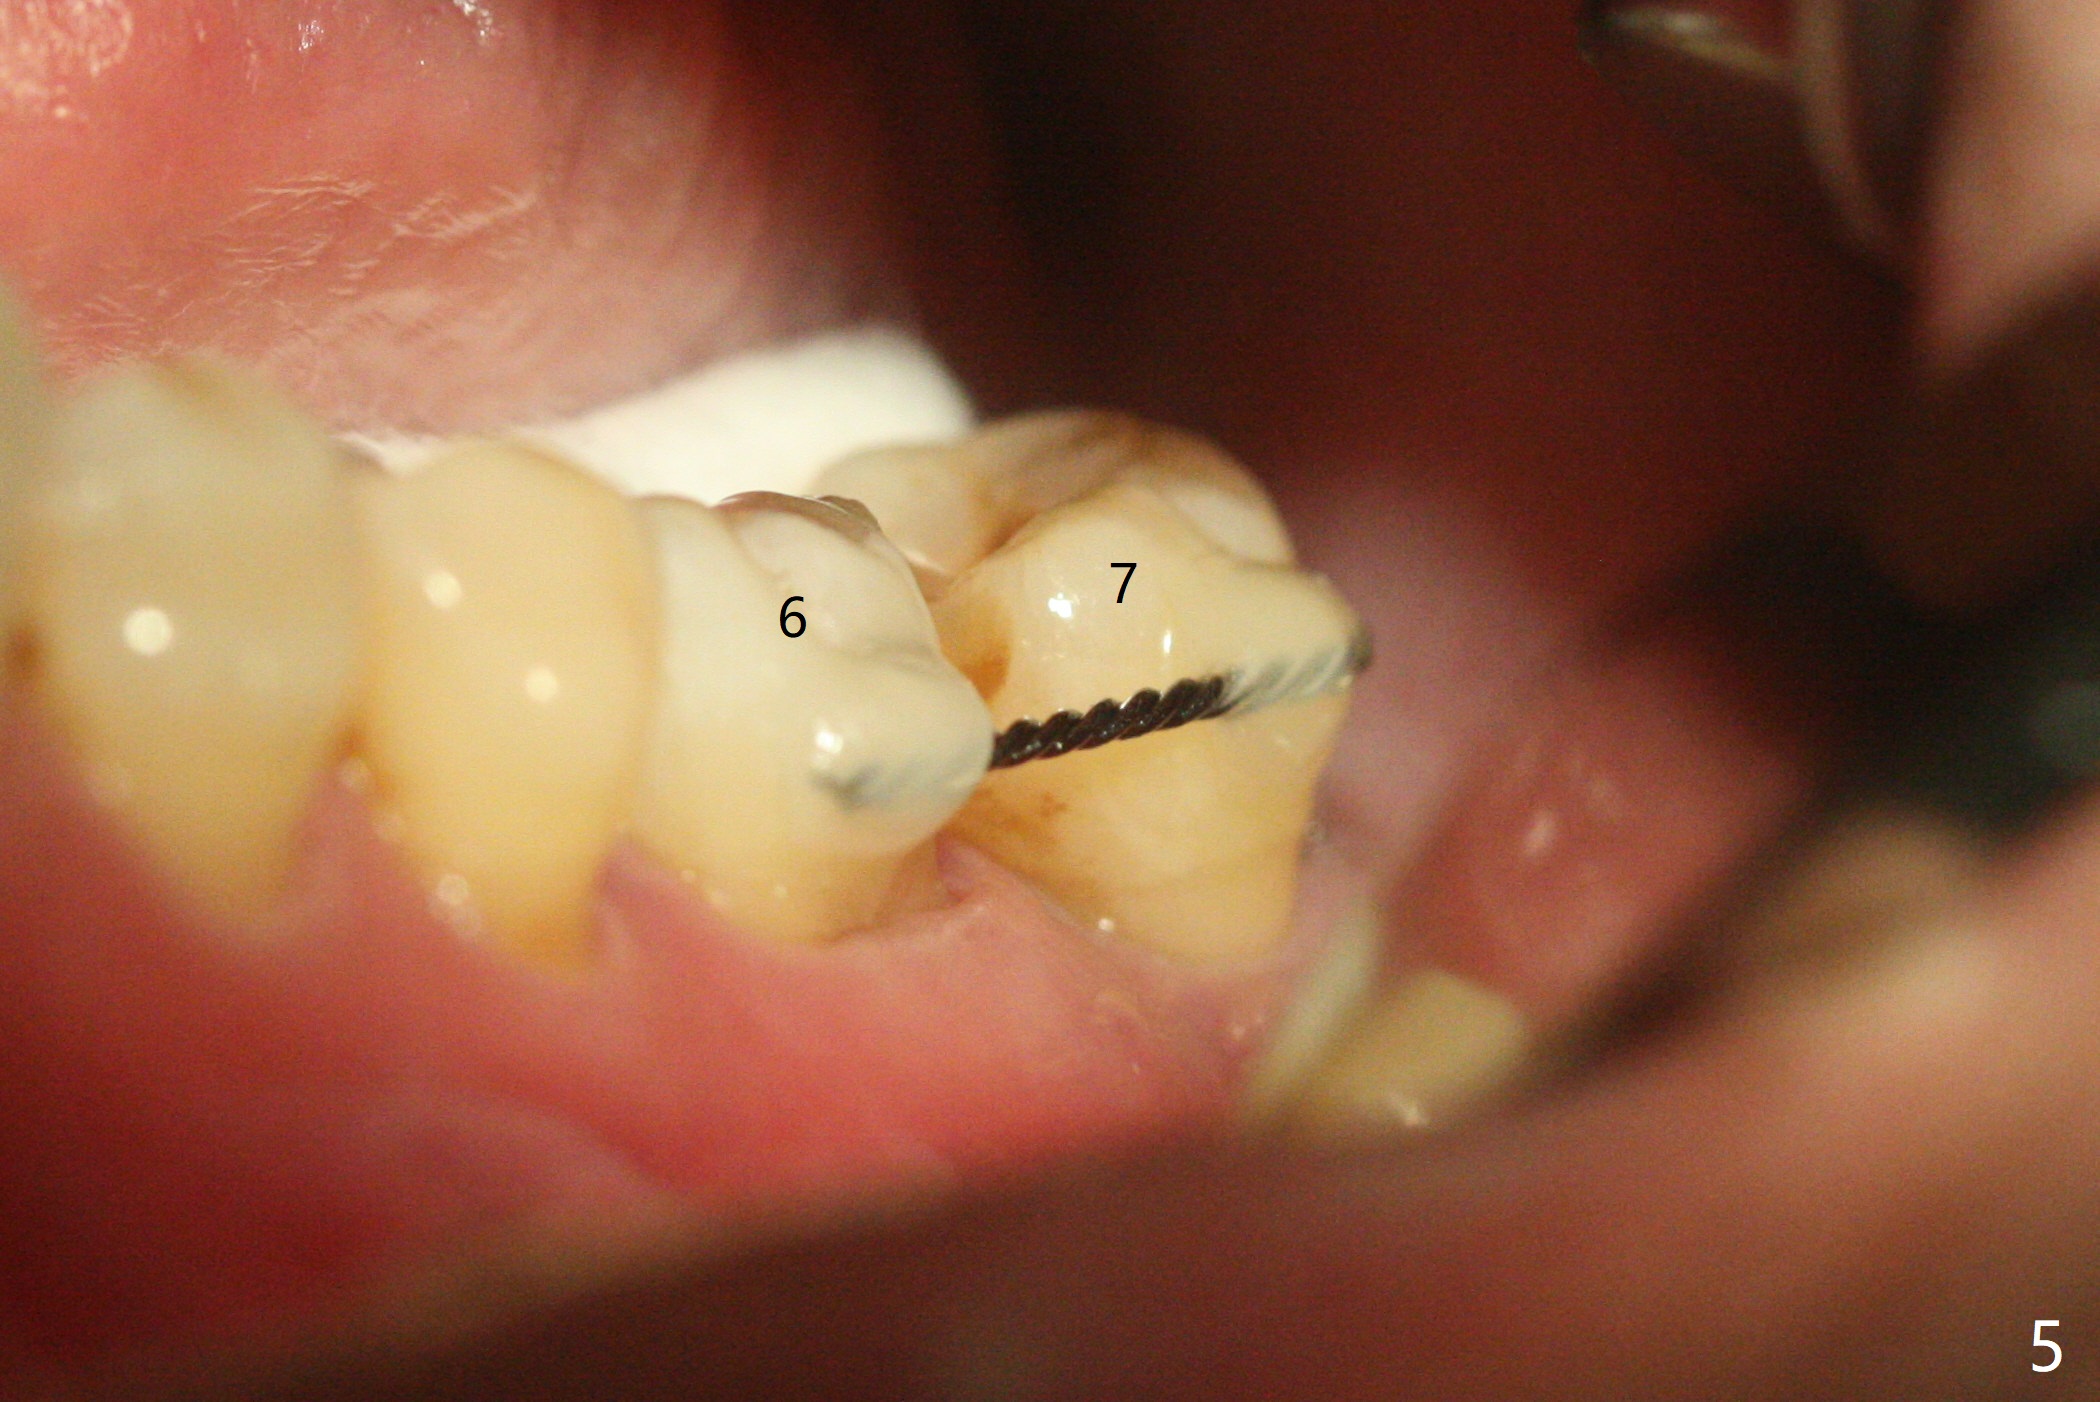

54岁男右下6,7拔除,延期种植十个月还没有完成,左下7松动(图一,二),准备即刻种植,有4-5毫米根尖骨质固定植体(图三,四),缩短治疗时间,但是必须逾越神经管,需要导板,植入偏细植体(4毫米),这样有2毫米安全地带(图四),为了减少植体过细造成植体断裂,使用五级钛植体。由于植体种得深,牙龈厚,基台袖需要长4或者5毫米(图三:粉红色),试用治疗性基台(4.5x4,4.5x15 degree A or B, 4mm),可能需要使用带角度基台(图四:蓝色),这样避免坚硬颊侧骨板,颊侧多放些粘性骨粉。第二次取模后,固定松动牙,让病人舒服些,之后必须调整咬合。